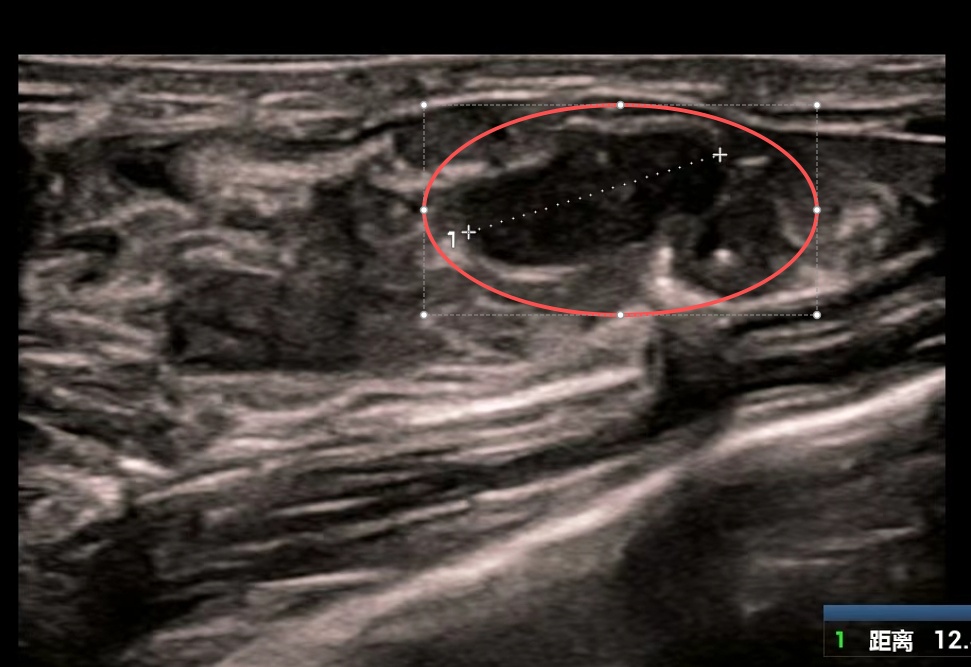

美美的检查结果让医生与家属心头一紧:她的双侧乳房内竟散落84个大小不一的肿块,其中最大一个达6厘米×5厘米,如同鹅蛋大小。

▲ 美美的影像检查部分截图,画圈位置为较大肿块

虽然彩超乳腺分级标准为3级,穿刺活检显示为良性结节,但如此庞大的数量和体积的肿块,已严重威胁乳腺健康,需手术处理。